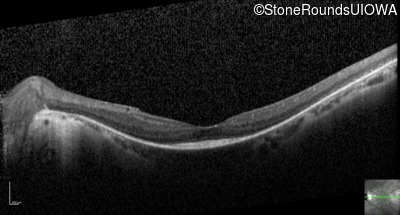

Optical Coherence Tomography - Left - 20/25

Exemplar / OCT Stack